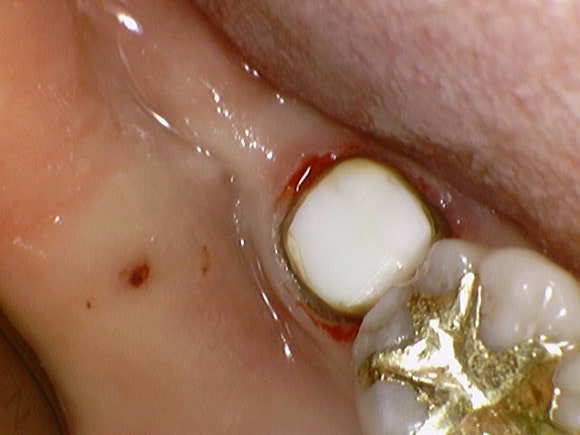

20250208

크라운을 제거해보니

얇은 금속 기둥이 하나 보입니다.

치과에서는 이를 포스트라고 부릅니다.

치아의 머리 부분이 많이 부족할 때,

뿌리에 이 기둥을 심어서

머리 부분을 지지해주는 역할을 합니다.

결론부터 말씀드리면

이번 재치료에서는 굳이 포스트를 식립하지 않았습니다.

그닥 필요해보이지 않아서요.